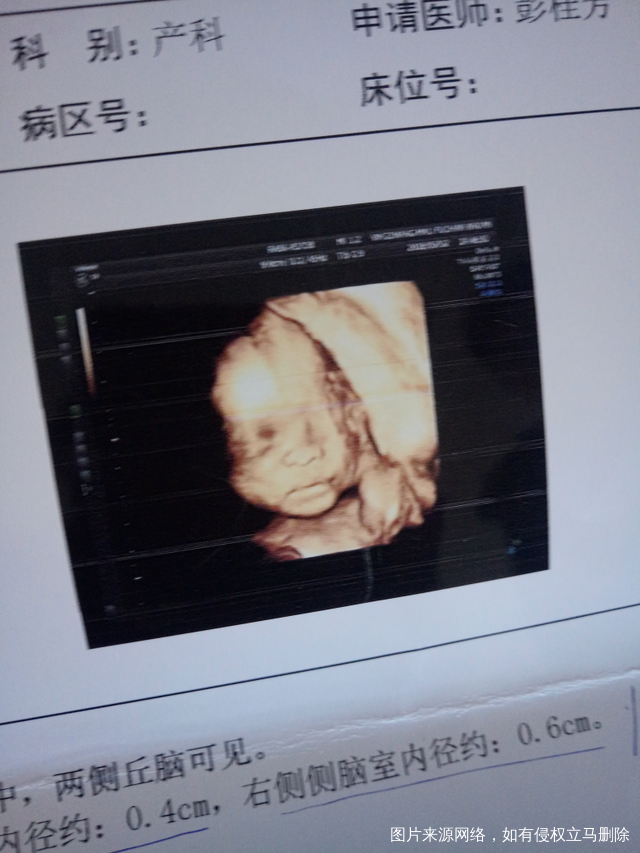

四维通过,折腾了一天,分不清

上午去了没拍到,下午去了就拍到了,分不清男女